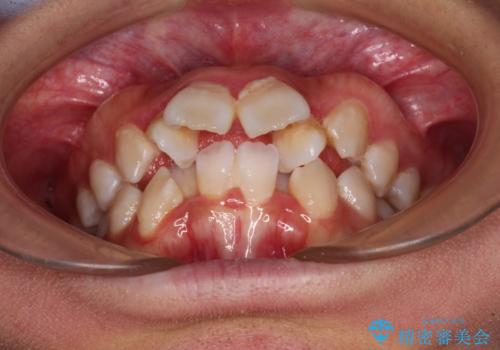

唇からはみ出るほど飛び出した前歯 ワイヤー装置による抜歯矯正

- 飛び出した上顎の前歯と八重歯を気にして来院された患者様です。

口元を積極的に引っ込めるために、上下左右の小臼歯計4本を抜歯することとしました。

舌の突出癖が強いため、しっかりと口元を引っ込めるため、舌のトレーニングをしっかりと行いながら矯正治療を行うこととしました。